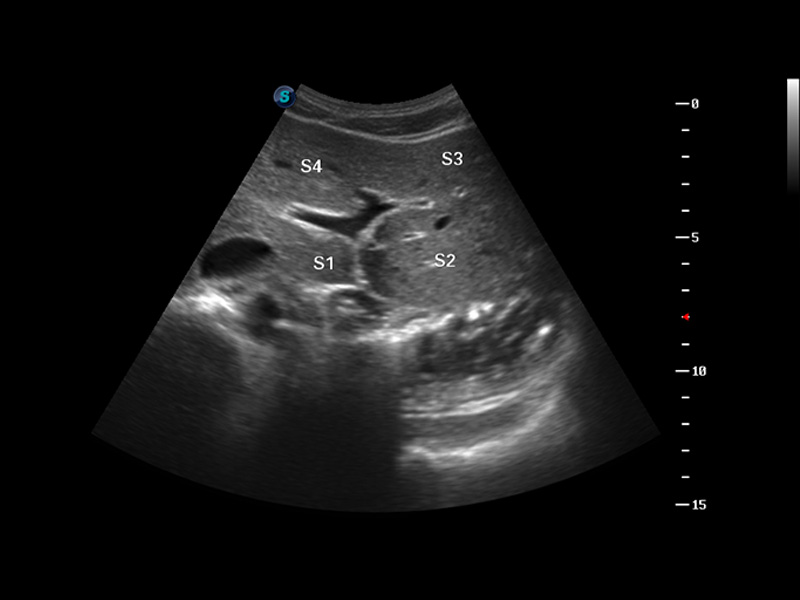

S8 EXP便携式彩色多普勒超声诊断仪是1xBET研发的高端全身应用型便携彩超。高通道的VIS平台融合可视化(Visual)、智能化(Intelligent)和人性化(Smart)的特点,配以1xBET自主研发生产的探头大家族,使您能够快速、准确的获得病人信息,提高工作效率的同时减轻疲劳。

谐波成像